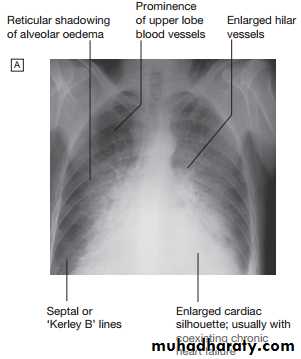

Serum urea, creatinine and electrolytes, haemoglobin, thyroid function, ECG and chest X-ray may help to establish the nature and severity of the underlying heart disease and detect any complications. Brain natriuretic peptide (BNP) is elevated in heart failure and is a marker of risk; it is useful in the investigation of patients with breathlessness or peripheral oedema. Echocardiography is very useful and should be considered in all patients with heart failureManagement of acute pulmonary oedema

Low cardiac output causes fatigue, listlessness and a poor effort tolerance; the peripheries are cold and the BP is low. To maintain perfusion of vital organs, blood flow is diverted away from skeletal muscle and this may contribute to fatigue and weakness. Poor renal perfusion leads to oliguria and uraemia. Pulmonary oedema due to left heart failure presents as above and with inspiratory crepitations over the lung bases. In contrast, right heart failure produces a high JVP with hepatic congestion and dependent peripheral oedema. In ambulant patients, the oedema affects the ankles, whereas, in bed-bound patients, it collects around the thighs and sacrum. Ascites or pleural effusion may occur